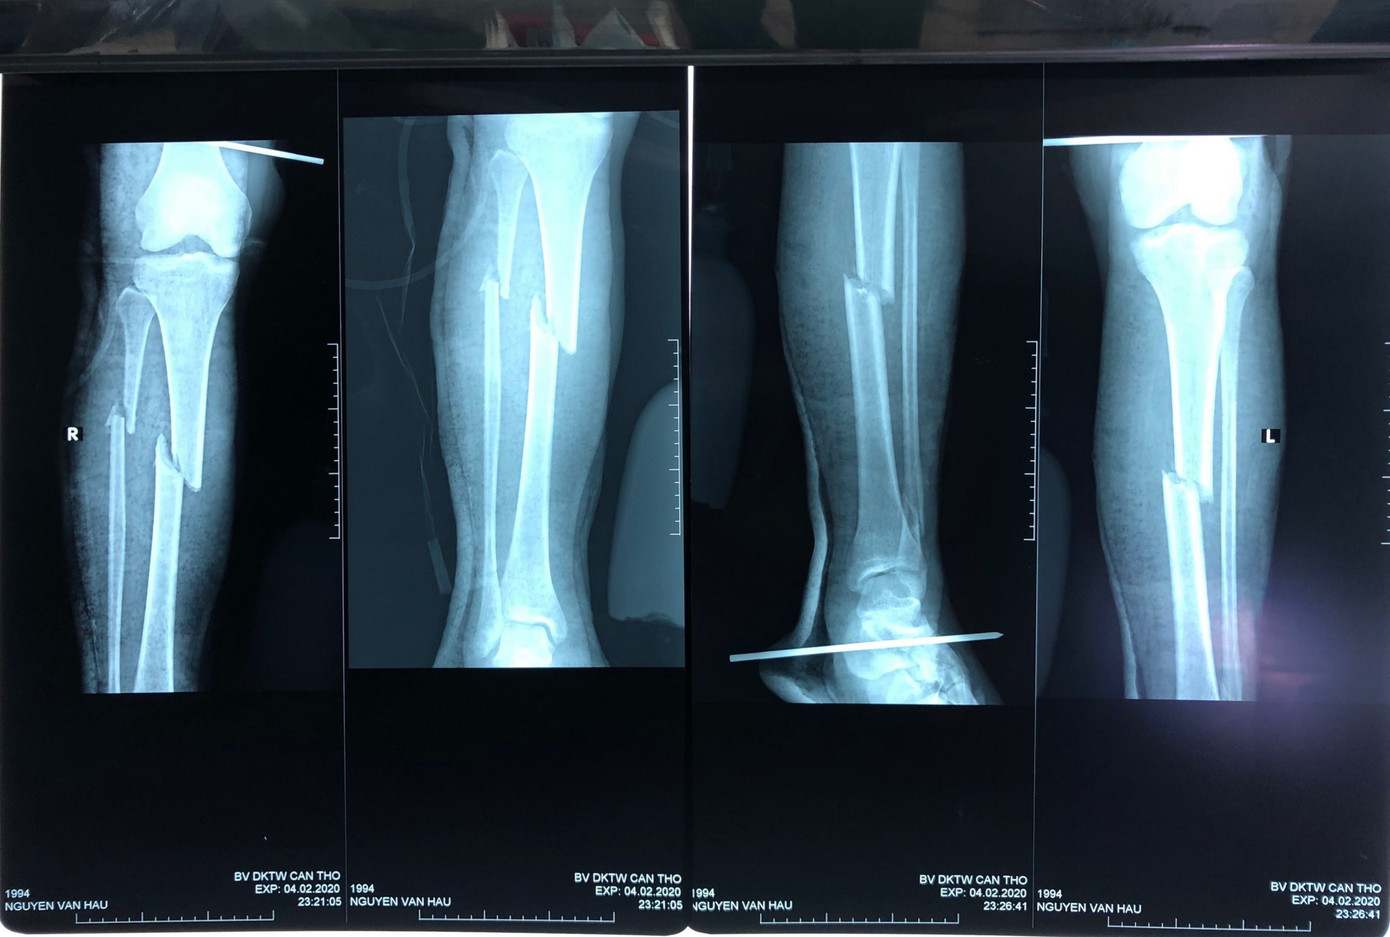

Tiếp nhận bệnh nhân, các bác sĩ đã nhanh chóng hội chẩn, chẩn đoán nam thanh niên bị đa tổn thương gãy hở mỏm khuỷu trái, hở xương đùi trái, bàn chân trái, gãy kín 2 xương cẳng chân trái, gãy kín xương đùi phải, gãy kín 2 xương cẳng chân phải. Đồng thời, có chỉ định phẫu thuật.

Phẫu thuật thành công ca gãy xương hiếm gặp ở 6 vị trí ảnh 2Nhiều vị trí xương bị gãy.

Ekip bệnh viện đã tiến hành 2 lần phẫu thuật để xử trí cắt lọc vết thương đùi trái do gãy hở và kết hợp xương cho bệnh nhân. Do mất quá nhiều máu nên tính đến thời điểm này, các bác sĩ đã truyền cho anh Hậu 8 đơn vị máu.

Bác sĩ CK2 Huỳnh Thống Em - Trưởng Khoa Ngoại chấn thương cho biết, theo y văn, gãy xương đùi và gãy xương chày cùng bên còn gọi là gãy bập bềnh gối. Đây là 1 tổn thương nặng do tính chất phức tạp của nó nên kết quả điều trị dễ ảnh hưởng tới phục hồi chức năng.

Trường hợp đặc biệt là gãy bập bềnh cả 2 gối là tổn thương rất hiếm gặp, theo y văn, chỉ có 3 ca được báo cáo. Đây là dạng gãy xương do chấn thương năng lượng cao. Bệnh kèm theo các tổn thương khác như đầu ngực bụng, đe dọa mạng sống của bệnh nhân, việc điều trị khó khăn và phải phục hồi trong thời gian rất dài.

Để giảm thiểu thời gian mổ, nguy cơ mất máu nhiều dễ gây rối loạn đông máu, thuyên tắc máu, các bác sĩ đã tiến hành phẫu thuật sớm cắt lọc và xử trí tổn thương gãy hở trước, để kiểm soát nguy cơ nhiễm trùng vết thương do gãy hở. Sau 4 ngày thực hiện lần mổ đầu tiên, tổng trạng bệnh nhân ổn định, đủ điều kiện đáp ứng cho cuộc phẫu thuật tiếp theo. Ekip một lần nữa tiến hành kết hợp xương bên trong cho chân còn lại bao gồm xương đùi, cẳng chân phải và mỏm khuỷu trái cho bệnh nhân.